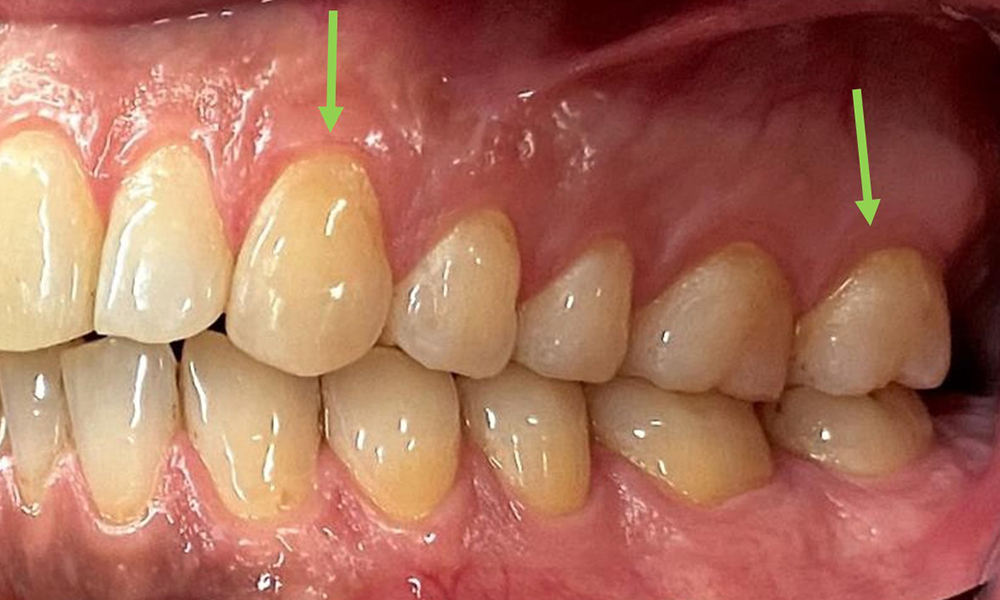

Extra- und Intraoraler Befund

Extraoral sind keine pathologischen Befunde festzustellen, intraoral zeigen sich bei der Frontalansicht im Bereich der keratinisierten Gingiva und am Übergang zur beweglichen Schleimhaut bräunlicheVerfärbungen (Abb. 2), welche auf den Nikotingenuss zurückzuführen sind. Am Gaumenbereich zeigen sich insbesondere im Bereich Oberkiefermolaren palatinal weißliche Schleimhautveränderungen, die ein Hinweis auf einen erhöhten Verhornungsgrad sind und ebenso auf den Nikotingenuss zurückzuführen sind. Die Zunge ist mit einem weiß-bräunlichen abwischbaren Belag versehen.